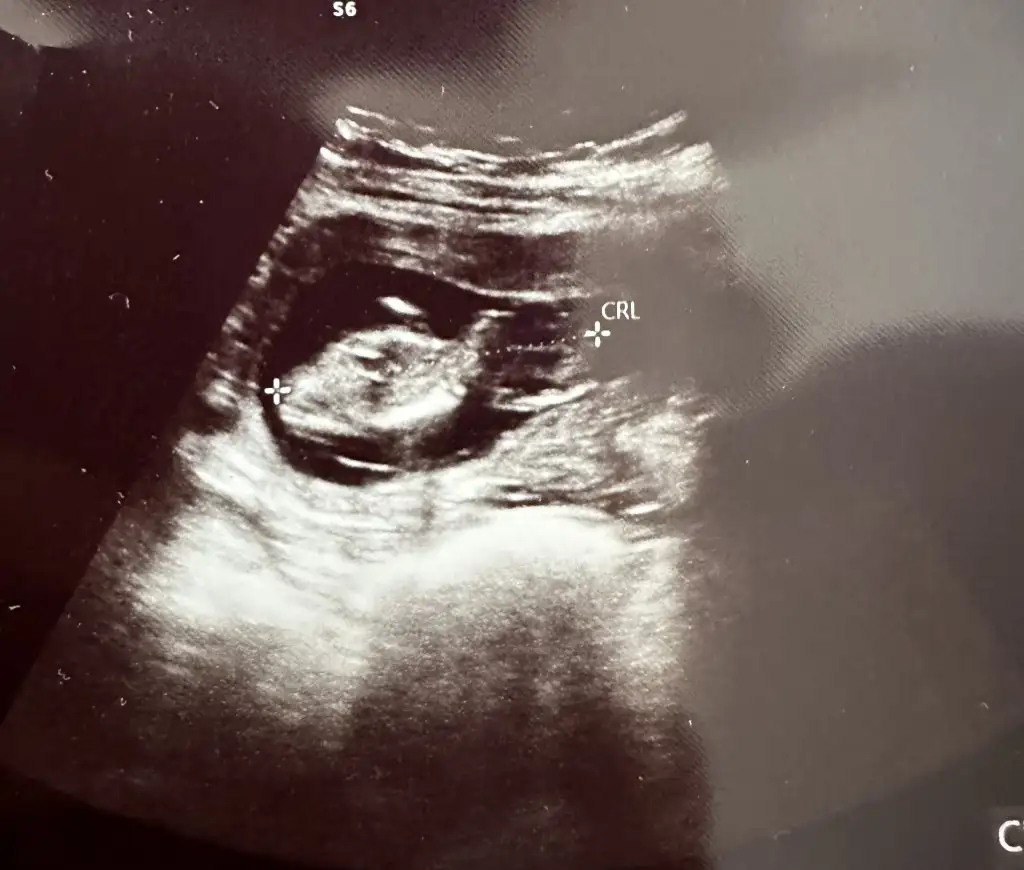

bende tahmin alabilir miyim

Eklentiler

• IMG_20220114_092252.webp

IMG_20220114_092252.webp

39,4 KB · Görüntüleme: 62

• IMG_20220114_092247.webp

IMG_20220114_092247.webp

36,8 KB · Görüntüleme: 70

sırtı dönük ama